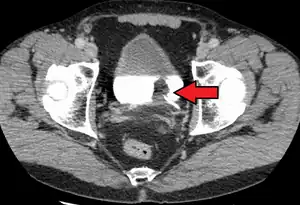

-

Bladder wall thickening due to cancer -